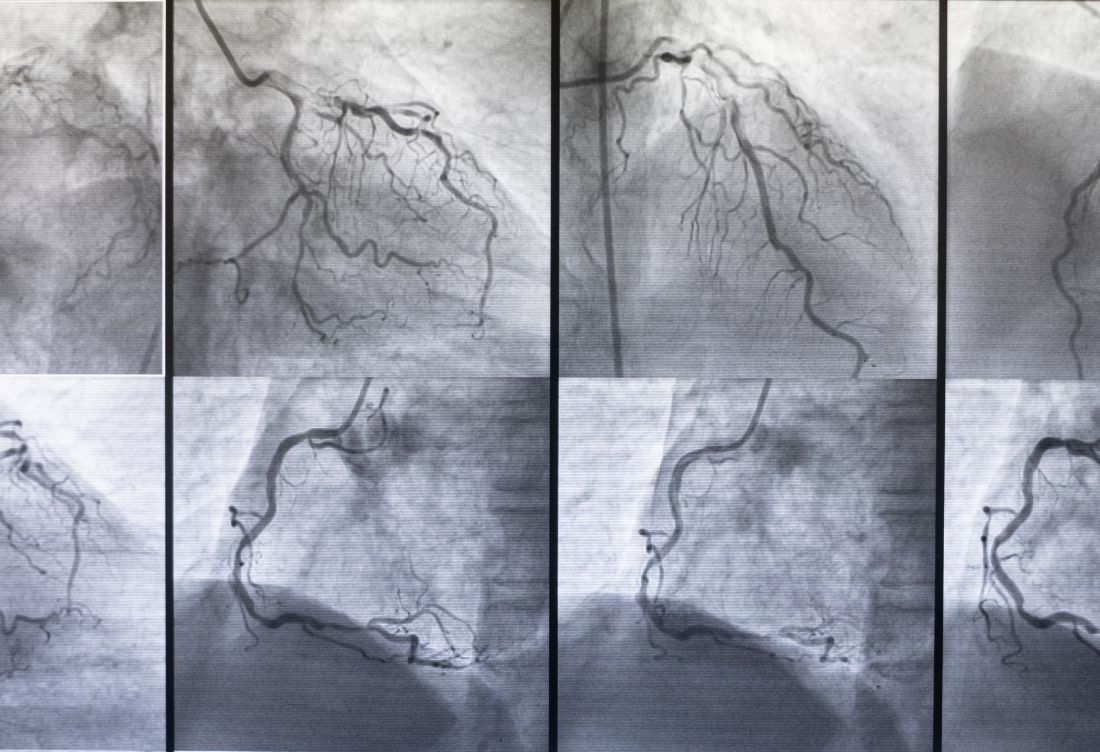

Koroner arter hastalığı, kalp kasınıza kan taşıyan koroner arterlerinizdeki (atardamarlarınızdaki) kan akışını sınırlamaktadır.